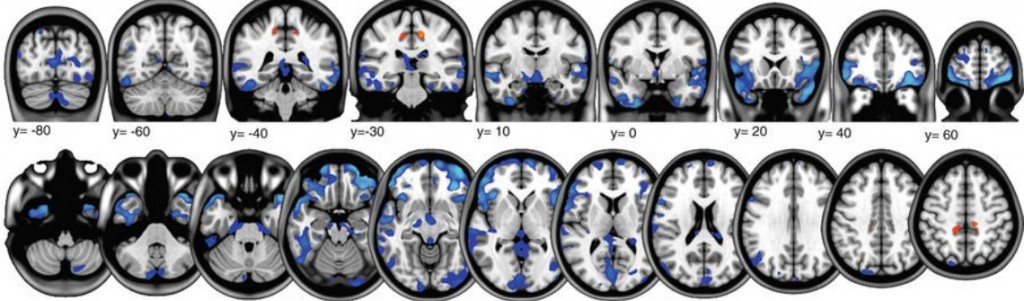

Les chercheurs ont constaté une diminution considérable du volume de matière grise dans le cerveau de ces astronautes. Notamment dans de grandes zones couvrant les lobes temporal et frontal et autour des orbites. À l’opposé, ils ont découvert une augmentation de la quantité de matière grise dans des zones plus localisées, notamment celles contrôlant le mouvement des membres inférieurs. Une augmentation ou une baisse de la matière grise dans différentes parties du cerveau a été relevée chez l’ensemble des astronautes. Plus ceux-ci avaient séjourné longtemps dans l’espace, plus les modifications étaient importantes.

La baisse de volume de matière grise pourrait être liée à la redistribution du liquide céphalo-rachidien dans l’espace, avancent les chercheurs. « La gravité n’est pas disponible pour extraire les liquides vers le bas dans le corps, ce qui se traduit par un visage dit gonflé dans l’espace. Cela peut entraîner un décalage de la position ou de la compression du cerveau», explique Rachael Seidler, auteur principale de l’étude et professeur de Kinésiologie et psychologie à l’Université du Michigan. En revanche, l’augmentation du volume de matière grise reflète probablement la plasticité cérébrale associée au fait d’apprendre à se déplacer en microgravité 24 heures sur 24. Une preuve supplémentaire que notre cerveau s’adapte à beaucoup de choses.